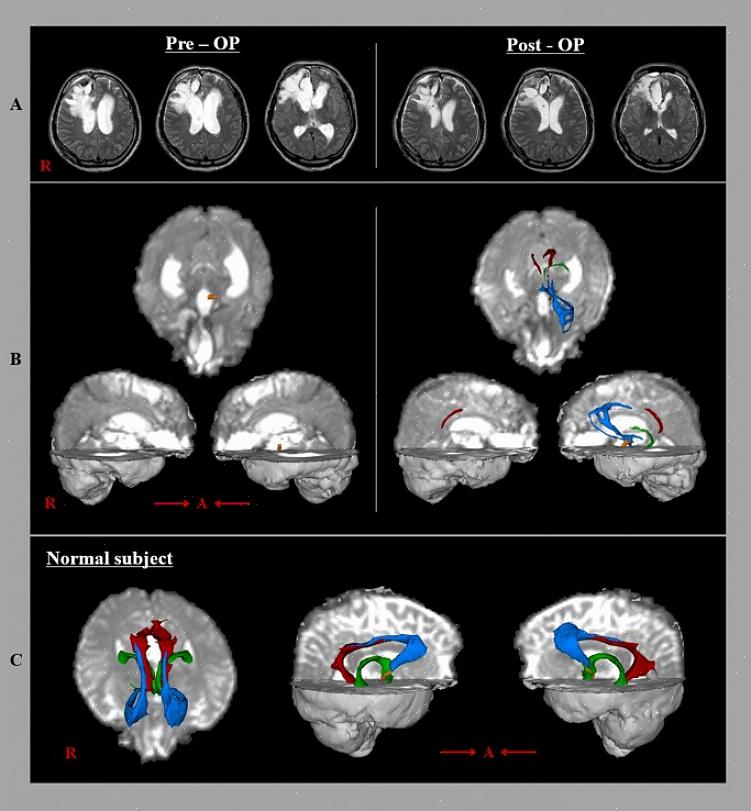

מעגל הפאפז מתחיל בהיווצרות ההיפוקמפוס או התת-ביקולום. לאחר מכן הוא עובר דרך גופי הממיל ומערכת הממילוטלמית, הידועה גם בשם מערכת ויק ד'אזיר. ואז הוא עושה סינפסות בגרעין התלמודי הקדמי. משם, הוא מגיע ל-cingulum. לאחר מכן הוא עובר דרך קליפת המוח האנטורינאלית וחוזר שוב להיווצרות ההיפוקמפוס. בסך הכל, גודלו כ-350 מילימטרים.